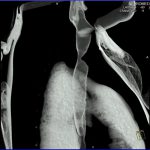

- Tumorilor cerebrale:

- Empiemul subdural

- Abcesul cerebral

- Fistula carotido-cavernoasa

- Higroma

- Atrofia cerebrală regională